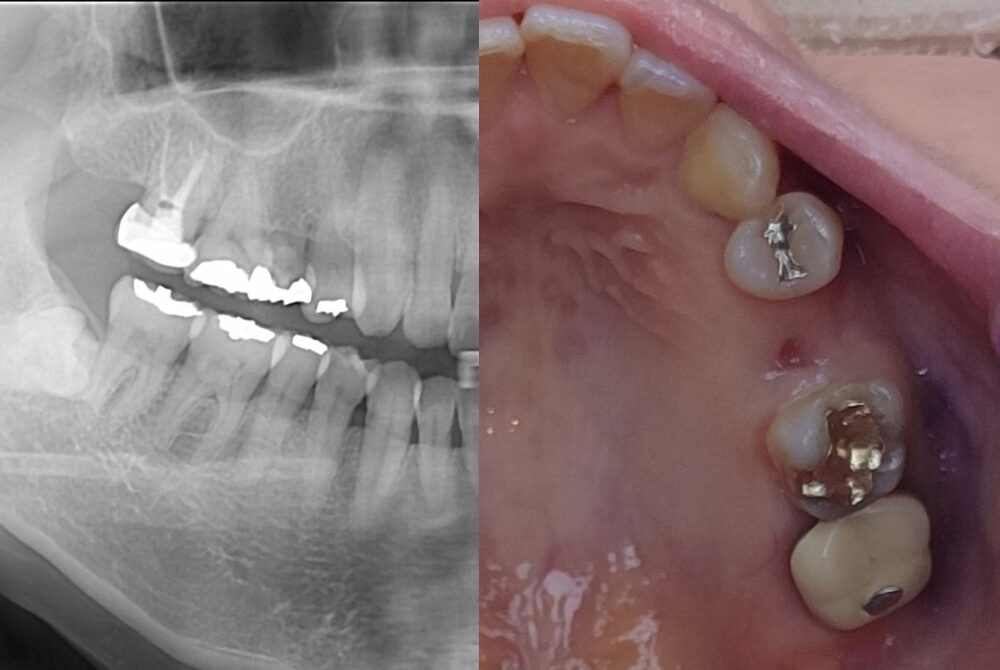

治療前

治療後

| 治療名称 | 右上のE番(残存乳歯)インプラント埋入/被せ物作成(ジルコニア) |

| 年齢・性別 | 40歳・女性 |

| 期間 | 5か月 |

| 費用 | 右上のE番(残存乳歯)インプラント埋入220,000円、被せ物作成 ジルコニア110,000円 |

| 治療内容 | ・患者の症状:残存乳歯の晩期であり、除去をして、インプラントを埋入 ・治療方法 :CT及びパントモレントゲンからインプラントの埋入位置を計測。麻酔下にてインプラント植立。仮歯を入れて約5か月待機。セレック治療にてジルコニアクラウンを製作、同日装着。 ・治療結果 :噛める歯が増えて、噛みやすくなる。 |

| 治療に伴うリスク | (リスク/副作用) 外科的な手術になる為、術後の腫れを伴うときがある。骨との癒着までの待機期間(2‐6カ月)がある。天然の歯と違い歯肉との関係が繊細であり、適切なケアをしなければインプラント周囲炎になる可能性がある。 |